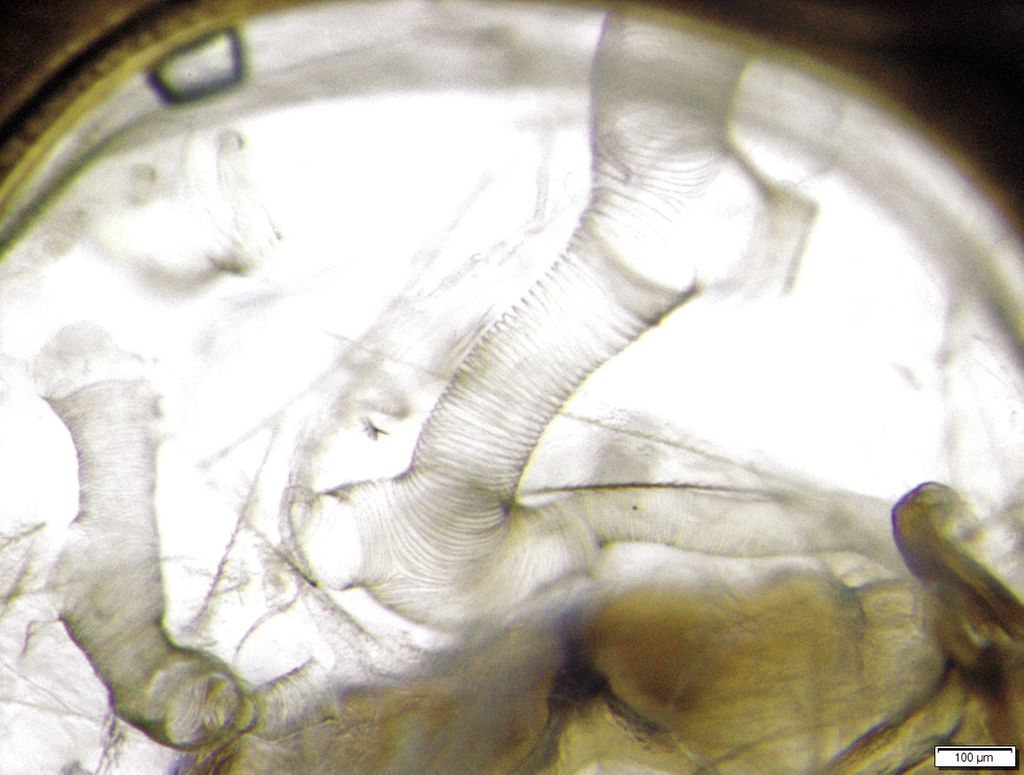

Acarapis woodi (foto 1) este un parazit obligatoriu care trăiește și se reproduce în prima pereche de tuburi traheale (foto 2, foto 3), a fost observat și la nivelul sacului aerian de cap, tors și abdominal. Parazitul este dioic.

Acarapis woodi se hrănește cu hemolimfa de albine care curge în interiorul tuburilor traheale din orificiile care apar ca urmare a acțiunii aparatului său bucal, pentru înțepat și supt, special construit.

Impactul negativ al parazitului asupra corpului unei albine infectate este rezultatul mai multor factori, printre care trebuie menționată obturarea parțială sau chiar completă a tuburilor traheale, datorită prezenței parazitului în ele, deteriorarea pereților tuburilor traheale, care poate fi poarta de acces a infecțiilor virale sau, în final, epuizarea asociată cu pierderea hemolimfei.

Foto 3. Sistemul traheal al albinelor. Fotograf Andrzej Bober

Se caută modificări în culoarea pereților tuburilor traheale (mieri punorme, modificări închise la culoare), rezultate din procesul de coagulare - așa-numita maleinizare a hemolimfei - în plus, se acordă atenție imaginii mușchilor adiacenți tuburilor traheale - dacă a existat o schimbare de culoare care ar putea indica o tulburare a funcționării lor.